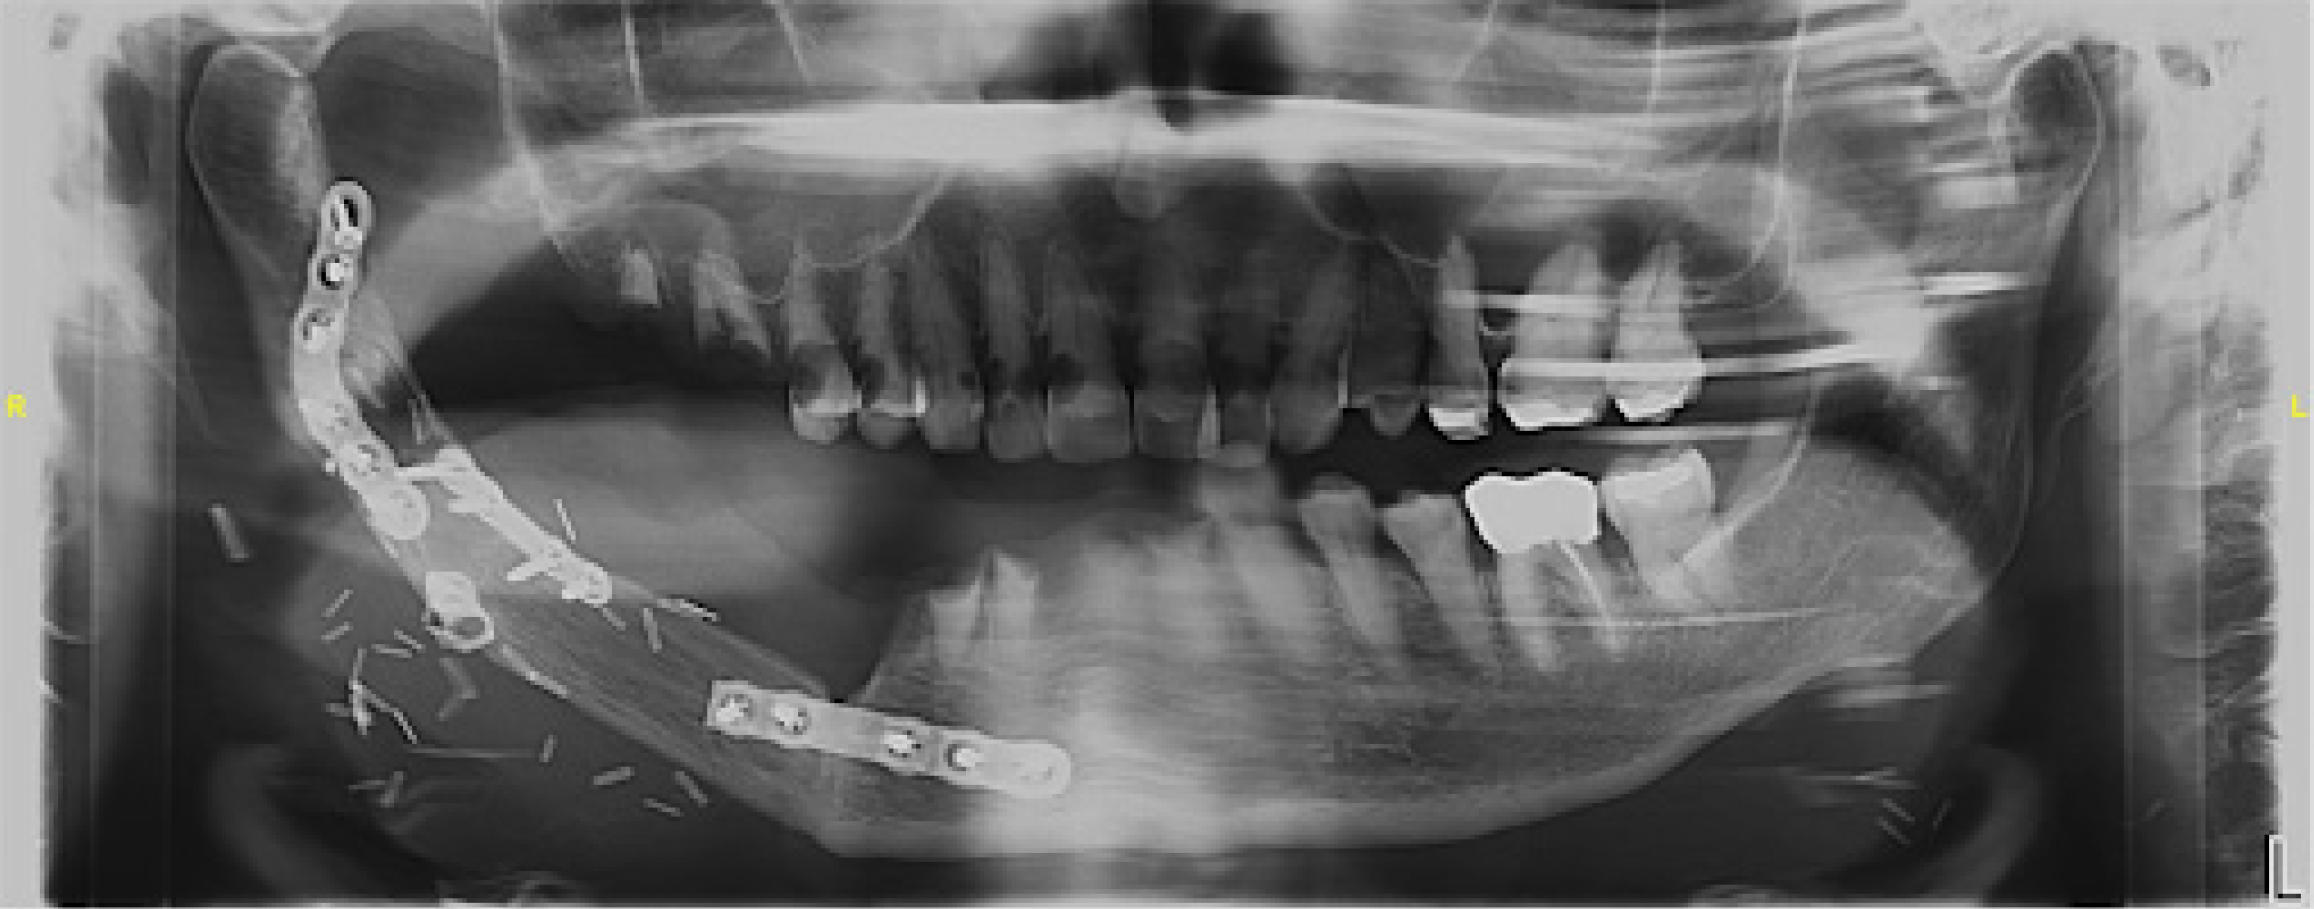

Radiographic evaluation confirmed the stability of the mandibular reconstruction with no evidence of malignant recurrence. However, due to restricted mouth opening, retroalveolar imaging was challenging. Panoramic and periapical radiographs revealed widespread carious lesions on teeth 15, 14, 13, 12, 11, 21, 22, 23, 24, 26, 33, and 37 (Figure 2).